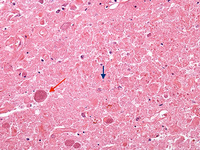

Biópsia de gânglios da base de paciente com meningoencefalite criptocócica exibindo expansão criptocócica (seta azul) de espaços de Virchow-Robbin em volta de um vaso lenticuloestriado (seta vermelha)

Do acervo pessoal de Robert E. Schmidt; usado com permissão